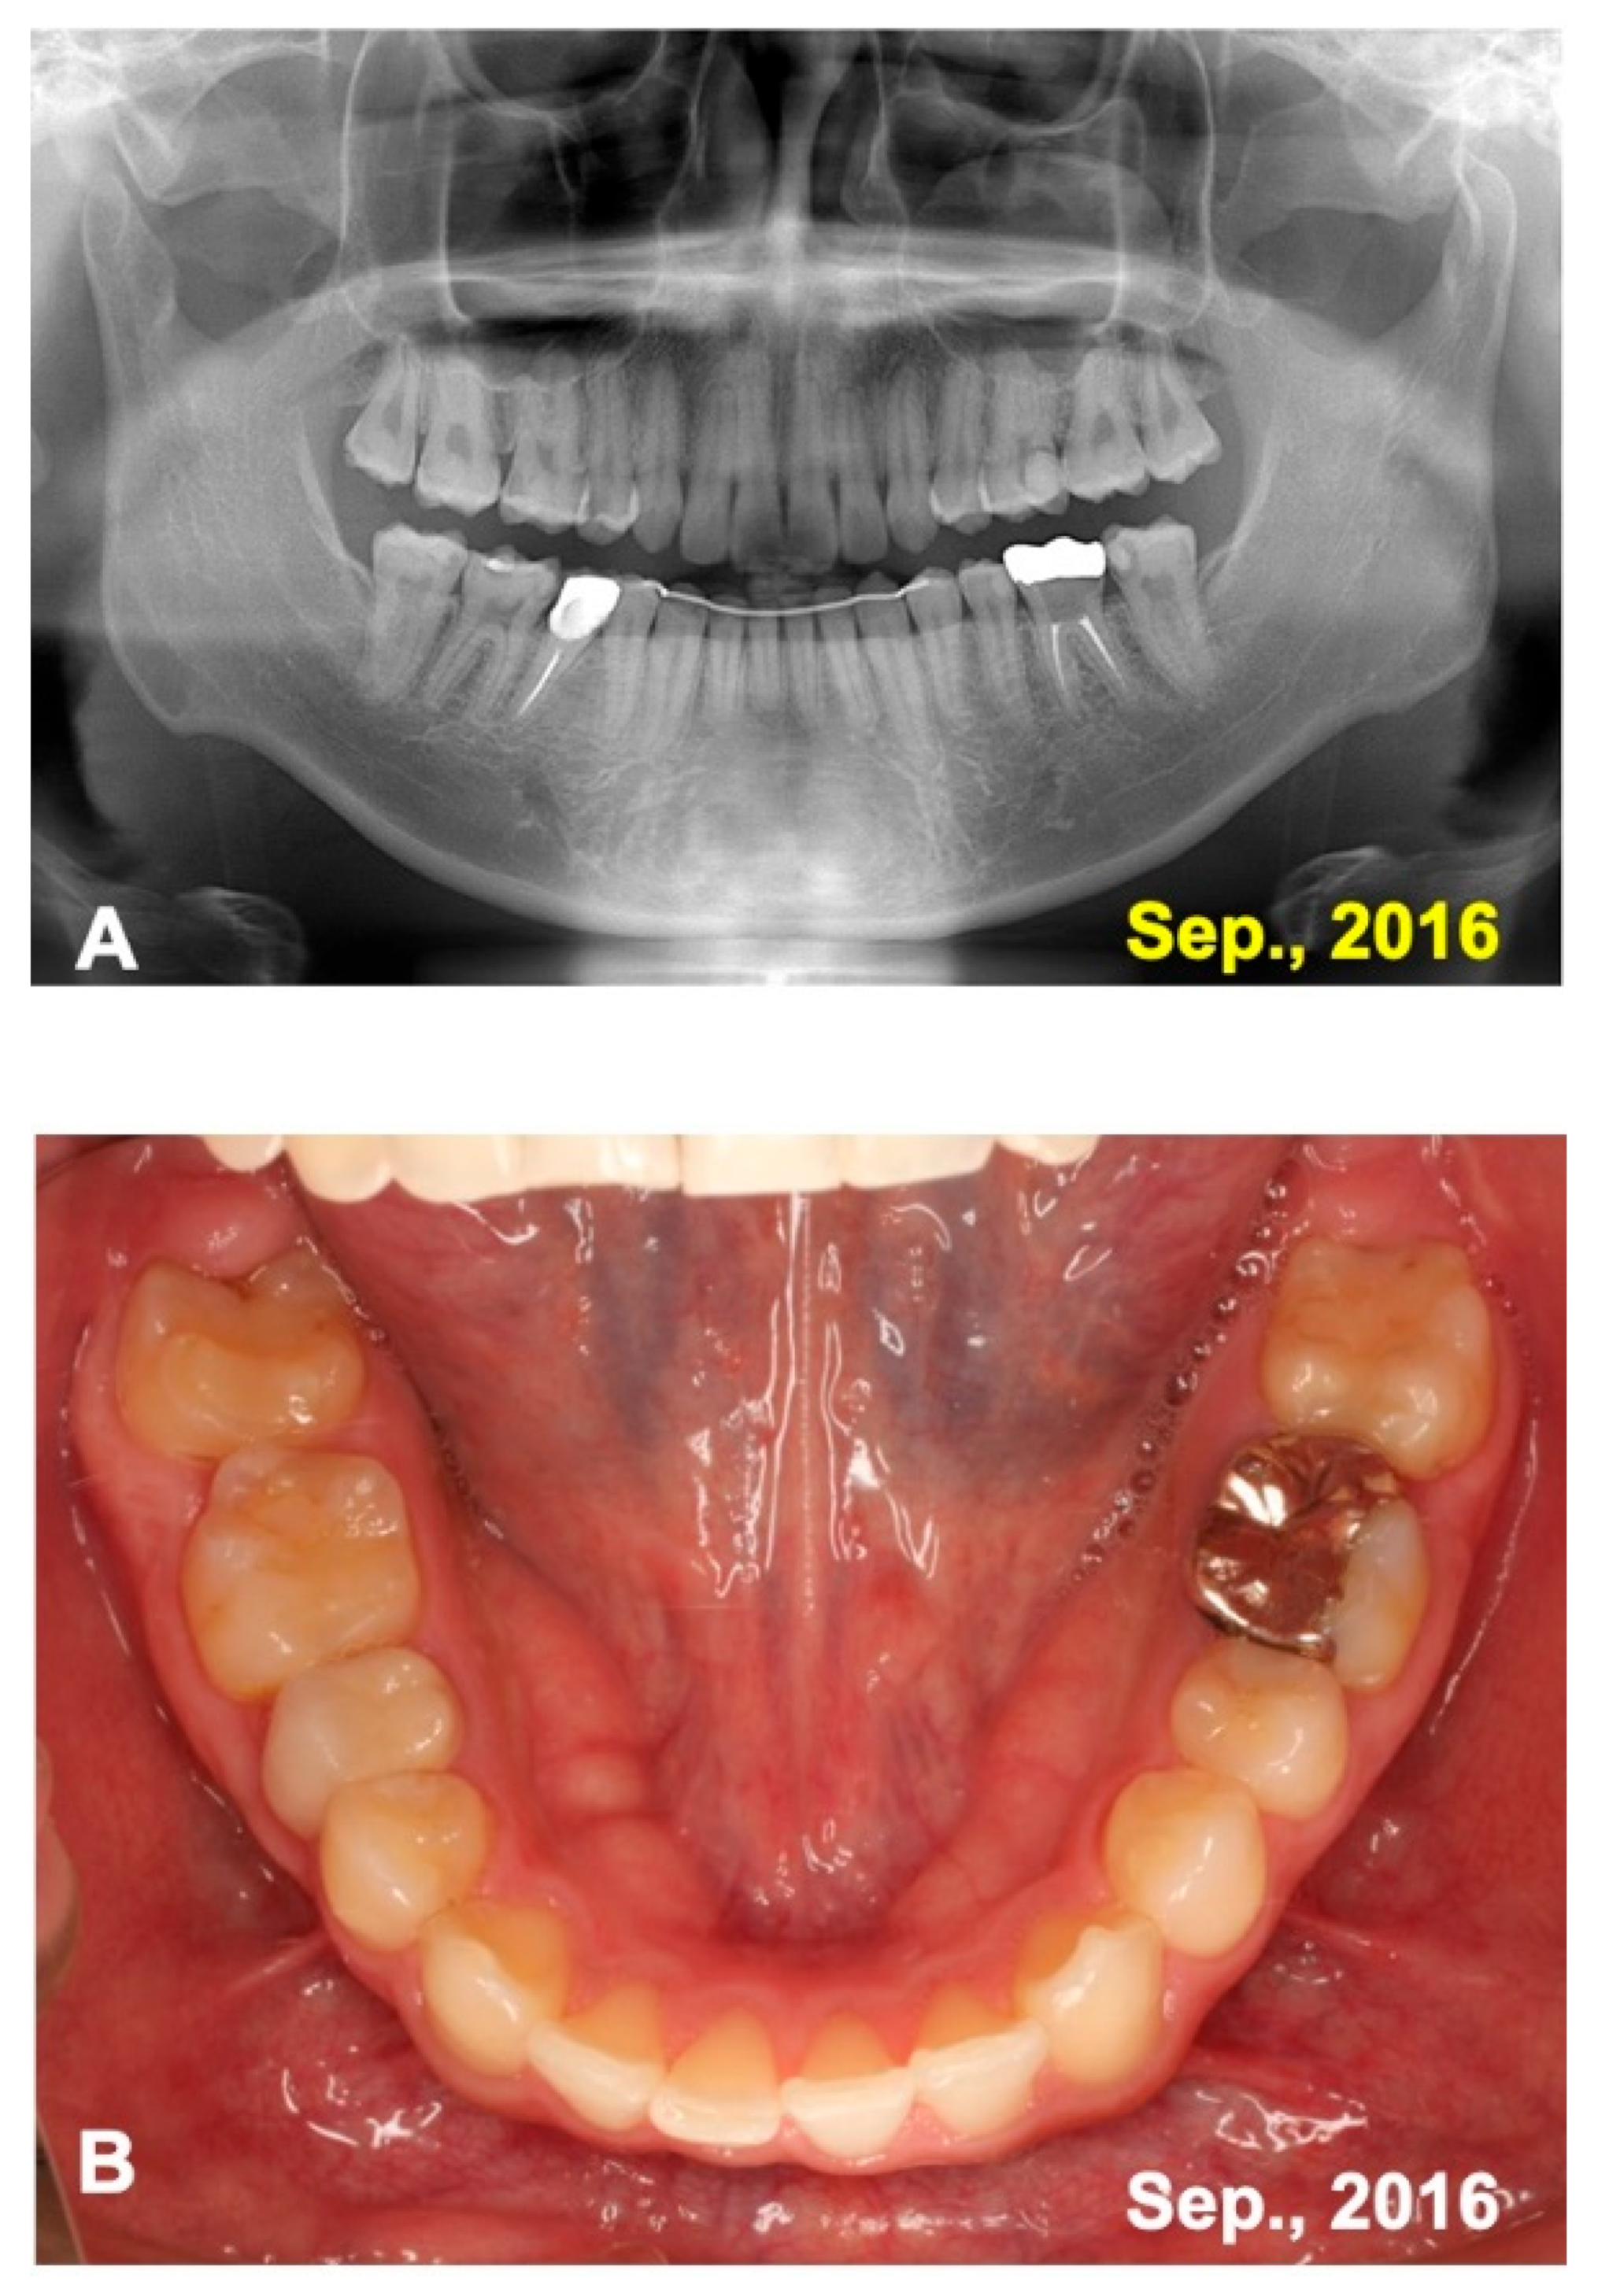

3. Results

3.1. Gross View and Examinations after Surgery

3.2. Radiographic Evaluation